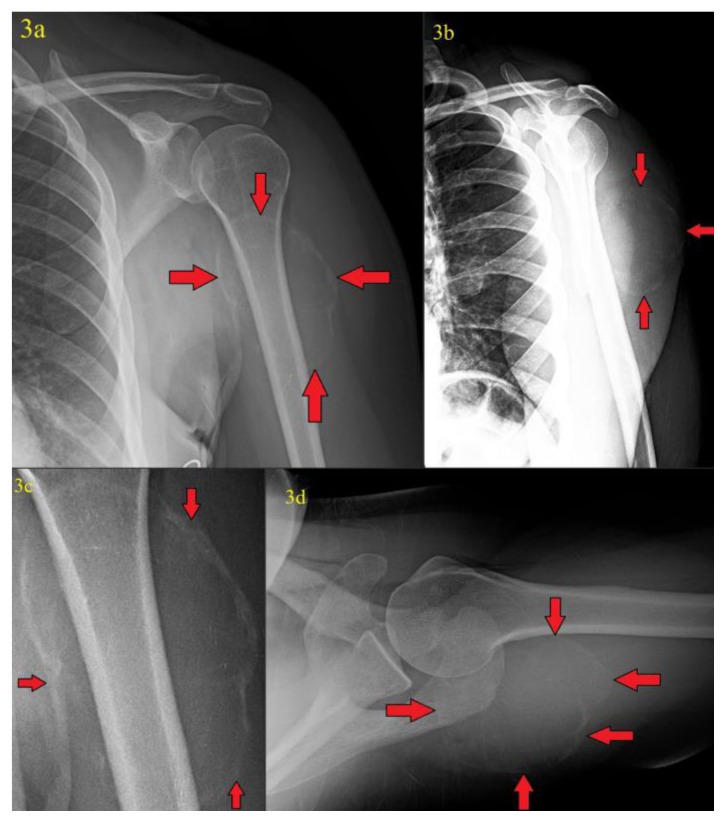

Figure 3.

41 year old female with a soft tissue aneurysmal bone cyst.

Findings: Internal rotation (figure 3a), scapular Y-view (figure 3b), magnification (figure 3c), and axial (figure 3d) radiographs of the left shoulder obtained 4 months after the patient’s initial presentation showed interim development of a 7.0 (transverse) cm × 5.5 (anteroposterior) cm × 6.7 cm (craniocaudad) cm peripherally calcified mass in the region of the posterior deltoid/upper triceps muscles (red arrows).

Technique: Radiographs were acquired on a GE® CR digital radiography unit with x-ray tube set at 70 kVp. Figure 3c is magnification view from figure 3a.